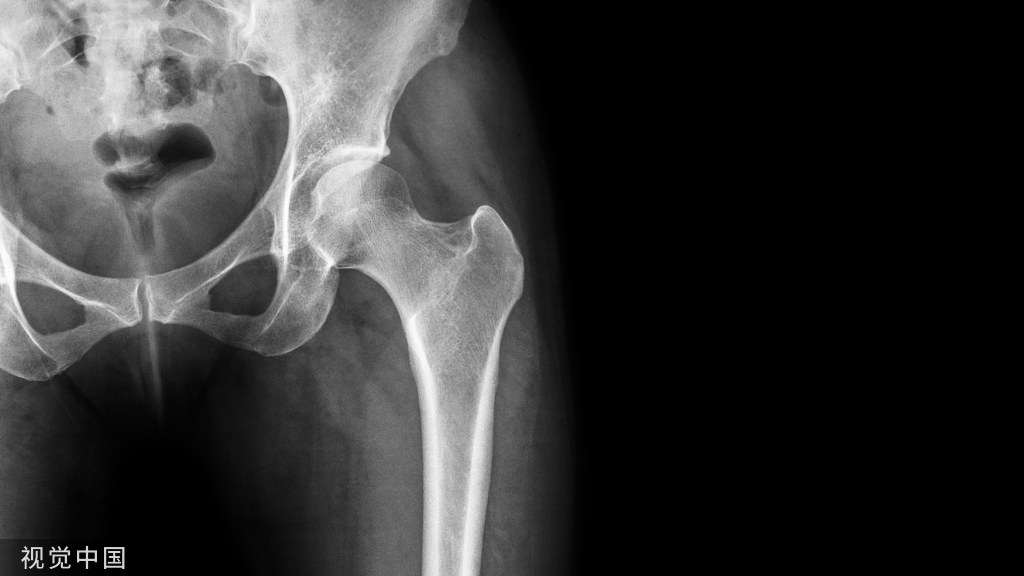

本研究旨在探讨桡骨远端和舟状骨合并骨折的特点,并确定手术和非手术治疗的结果差异。

桡骨远端骨折是一种非常常见的损伤类型。涉及桡骨远端骨折占所有骨折的六分之一,2001年仅在美国就有超过64万例报告。关于孤立性桡骨远端骨折的流行病学、分类、治疗和并发症有广泛的研究。然而,关于桡骨远端和舟状骨同时骨折的讨论很少,文献中发表的病例总数只有163例。其中,自2002年引入掌侧锁定钢板以来,仅有70例病例被报道。

据报道,同侧舟状骨骨折的发生率高达所有桡骨远端骨折的4%-4.7%。在163例报告病例中,4%的桡骨远端和舟状骨同时骨折的发生率表明,在我们目前的文献中,这种损伤模式被严重低估。

由于舟状骨和桡骨远端骨折复位发生在相反的方向,这种骨折模式呈现出独特的围期和术后处理困难。桡骨远端骨折复位需要纵向牵引和伸展至屈曲运动,而舟状骨则需要压缩。在此过程中,桡骨远端复位操作理论上可以使舟状骨移位。在这些骨折的手术或非手术治疗过程中,相互竞争的力量对治疗提出了挑战。